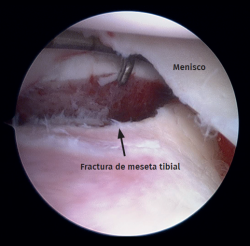

Meniscal tears were the most frequent soft tissue lesion (Figure 4), noted in 26 of the 40 patients evaluated (65.0%). The highest meniscal tear rate was seen in type II tibial plateau fractures (type I: 15.3%; type II: 80.7%; type III: 4%). Table 1 shows the number of meniscal injuries for each fracture type.

Figure 4. Left knee. View from the anterolateral portal. Peripheral longitudinal tear involving the lateral meniscus body.